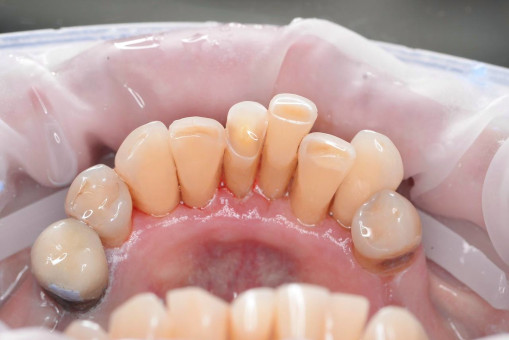

А прежде, чем вы посмотрите фотографии «до» и «после» лечения слизистой оболочки полости рта, проведенных в нашей клинике, хочу поблагодарить большое количество наших пациентов, которые поверили, прониклись нашей концепцией, и мы вместе, именно вместе победили болезни десны, гингивит и пародонтит!

До/после лечения